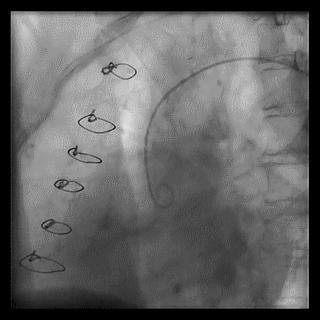

2014年,Patel T等首先采用球囊辅助通过技术(Balloon-assisted tracking,BAT),用于通过桡动脉途径中扭曲、细小节段(包括严重痉挛节段)(图1-2)。

图1

图2 BAT技术应用实例1。52岁女性患者冠脉严重痉挛(A),注射2次鸡尾酒后仍未缓解(B),采用BAT技术(C),顺利介导7F指引导管通过桡动脉严重痉挛节段(D)